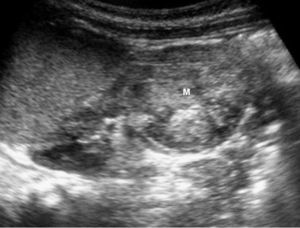

El tumor rabdoide se presentó en un niño de 5 meses estudiado por masa abdominal palpable y hematuria, con el antecedente de un hermano gemelo fallecido poco tiempo antes por tumor cerebral. El estudio con ecografía y TC abdominal demostró una masa renal sólida, heterogénea e hipodensa con poco realce. Se completó el estudio con ecografía transfontanelar y TC craneal identificando una masa cerebral sincrónica, intraaxial, frontal paramedial, sólido-quística con calcificaciones (fig. 7). No se conoció la histología del tumor cerebral por seguimiento del paciente en otro centro.

Fig. 7 Tumor rabdoide. Niño de 5 meses con hematuria y masa abdominal. (A) Ecografía abdominal. Corte longitudinal renal izquierdo. Masa sólida, heterogénea (M), bien delimitada en polo inferior de riñón izquierdo. (B) Tomografía computarizada abdominal con contraste intravenoso. Masa renal hipodensa, de aspecto infiltrativo, con crecimiento extrarrenal y tenue captación de contraste. (C) Tomografía computarizada craneal. Masa intraaxial, sólido-quística, fronto-temporal derecha, que desplaza la línea media, con un área de calcificación periférica.